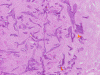

Pathology of the Case: Multiple tissue samples were from several locations of the sinuses were rerceived. The specimen was in the form of small aggregates of irregularly shaped, tan brown, necrotic debri with clotted blood and purulent material. Admixed with the soft tissue were small fragments of bone. Frozen section of “left nasal contents” reveals fungal organisms with hyphae and nonviable collagenous tissue, suspicious for invasive fungal infection. On permanent sections, about 99% of the tissue is composed of necrotic debri. There is an abundance of fungal organisms.  While some of the organisms are scattered, there are areas suggestive of an angioinvasive pattern. These organisms may well be recognized by hematoxylin and eosin stain but also well demonstrated by PAS and GMS stain. The organisms contain pauciseptate, “ribbon-like,” irregular hyphae with acute and right-angle branching. Associated with the hyphae are globus-shaped, pigmented sporangia  and columella (Panel C, D, and E). The hyphae are wide and here show acute angle branching. Occasional septum can be seen (Panel  D and E). The sporangium on the left shows angulated sporangiospores (Panel C and E). These features are characteristic of the class Zygomyycetes, order Mucorales. This order includes the Rhizopus and Mucor species. Fungal culture identified a Rhizopus specie as well as Aspergillus. The pathologic features are most compatible with a sino-nasal mixed fungal infection in an immunocompromised host.